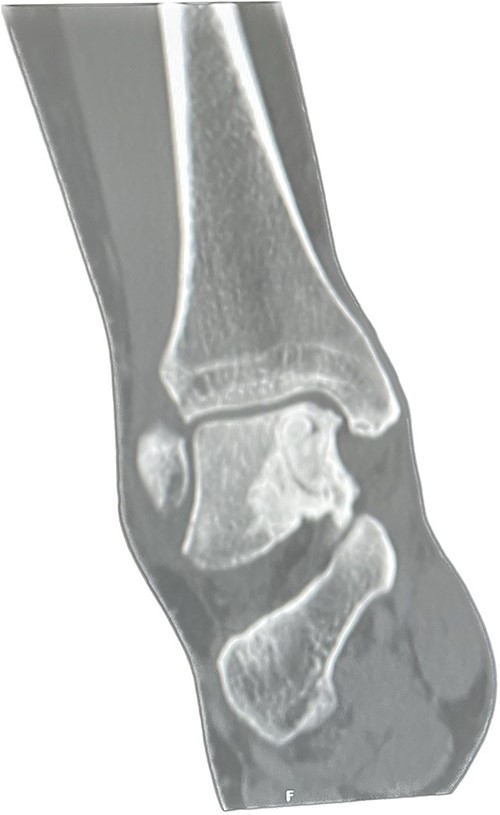

A CT scan was performed 6 months later, which showed that more than 50% of the cyst was replaced by bone substitute material and integrated with the surrounding trabecular network (Fig. 3). The patient was pain-free and walked without any discomfort at the 1-year follow-up appointment. The range of motion in her ankle was preserved, and she was able to function better at work. Moreover, her MOXFQ score reduced to 28/80 (Table 1) at the 1-year follow-up.